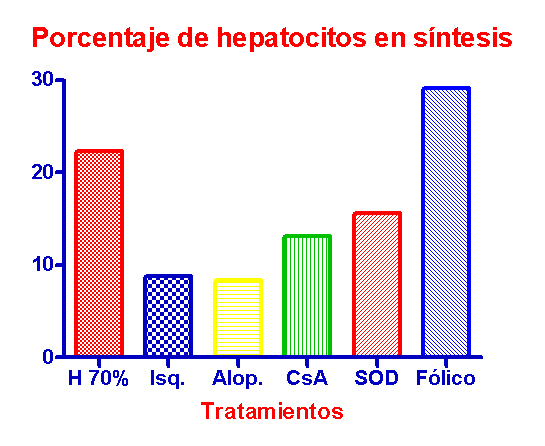

| 4 | Estudio del defecto de fármacos antioxidantes sobre la tasa regenerativa basal en el hígado sometido a isquemia normotérmica. El ácido fólico y la súperoxido dismutasa se demuestran efectivos; el alopurinol no produce ningún efecto. |

| 5 | La ciclosporina y el ácido fólico mejoran la respuesta regenerativa tras hepatectomía practicada en un hígado sometido a isquemia normotérmica. |

XXVII Congress of the European Society for Surgical Research. Zaragoza, 1.992. Antioxidant therapies and ischemic liver regeneration. V. Portugal, I. García-Alonso,P. Barceló, J. Bilbao, I. Iturburu, J. Méndez VII Congreso de la Sociedad Española de Investigaciones Quirúrgicas. Pamplona, 1.992. Regeneración del hígado isquémico y tratamientos antioxidantes. V.Portugal; I. García-Alonso; J. Bilbao; P. Barceló; I. López de Tejada; J. Méndez.

La ciclosporina y el ácido fólico

mejoran la respuesta regenerativa tras hepatectomía practicada en un hígado

sometido a isquemia normotérmica.